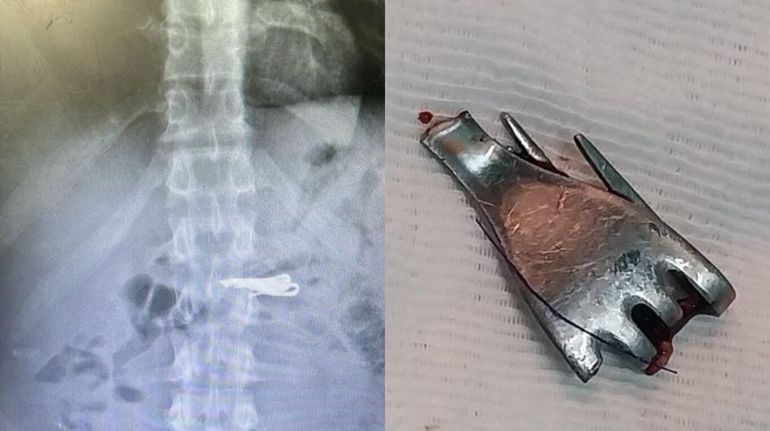

Meses atrás se conoció un caso similar al del interno de Piñero. A mediados del mes de agosto, un detenido que estaba alojado en el Complejo Penitenciario de Rosario, en el extremo oeste de la ciudad, se tragó una bombilla de mate en horas de la noche. Tuvo que ser trasladado al Hospital Eva Perón de Granadero Baigorria, donde fue operado con éxito, ya que los médicos lograron sacarle el elemento.

Identificado como Oscar Fabián Rodríguez (35), tuvo que pedir asistencia médica a causa de una dolencia estomacal, y fue llevado de urgencia hasta el hospital, donde se corroboró en una placa radiográfica que había ingerido una bombilla. El utensillo había quedado atravesado en la zona toracoabdominal.

El presidiario oriundo de Venado Tuerno, luego de haber sido intervenido quirúrgicamente, quedó internado en observación, a la espera de una evolución favorable.